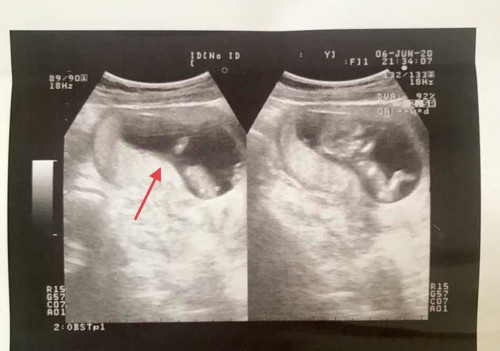

หมอว่าผู้ชาย แต่หนูเพิ่ง3เดือนเองนะ

หมอซาวด์แล้วทักว่านี่เด็กผู้ชายนะแม่ กลัวจะคลาดเคลื่อนจังค่ะ เพราะเพิ่ง 12w2d เป็นไปได้มั้ยคะอยากถามคุณแม่ที่มีลูกชายค่ะ

ตามภาพดูไม่ชัดนะคะ เพราะดูไม่เก่ง แต่ก็เห็นเหมือนจู๋นิดๆ 😂 และหมอน่าจะดูออก เลยบอกแบบมั่นใจ